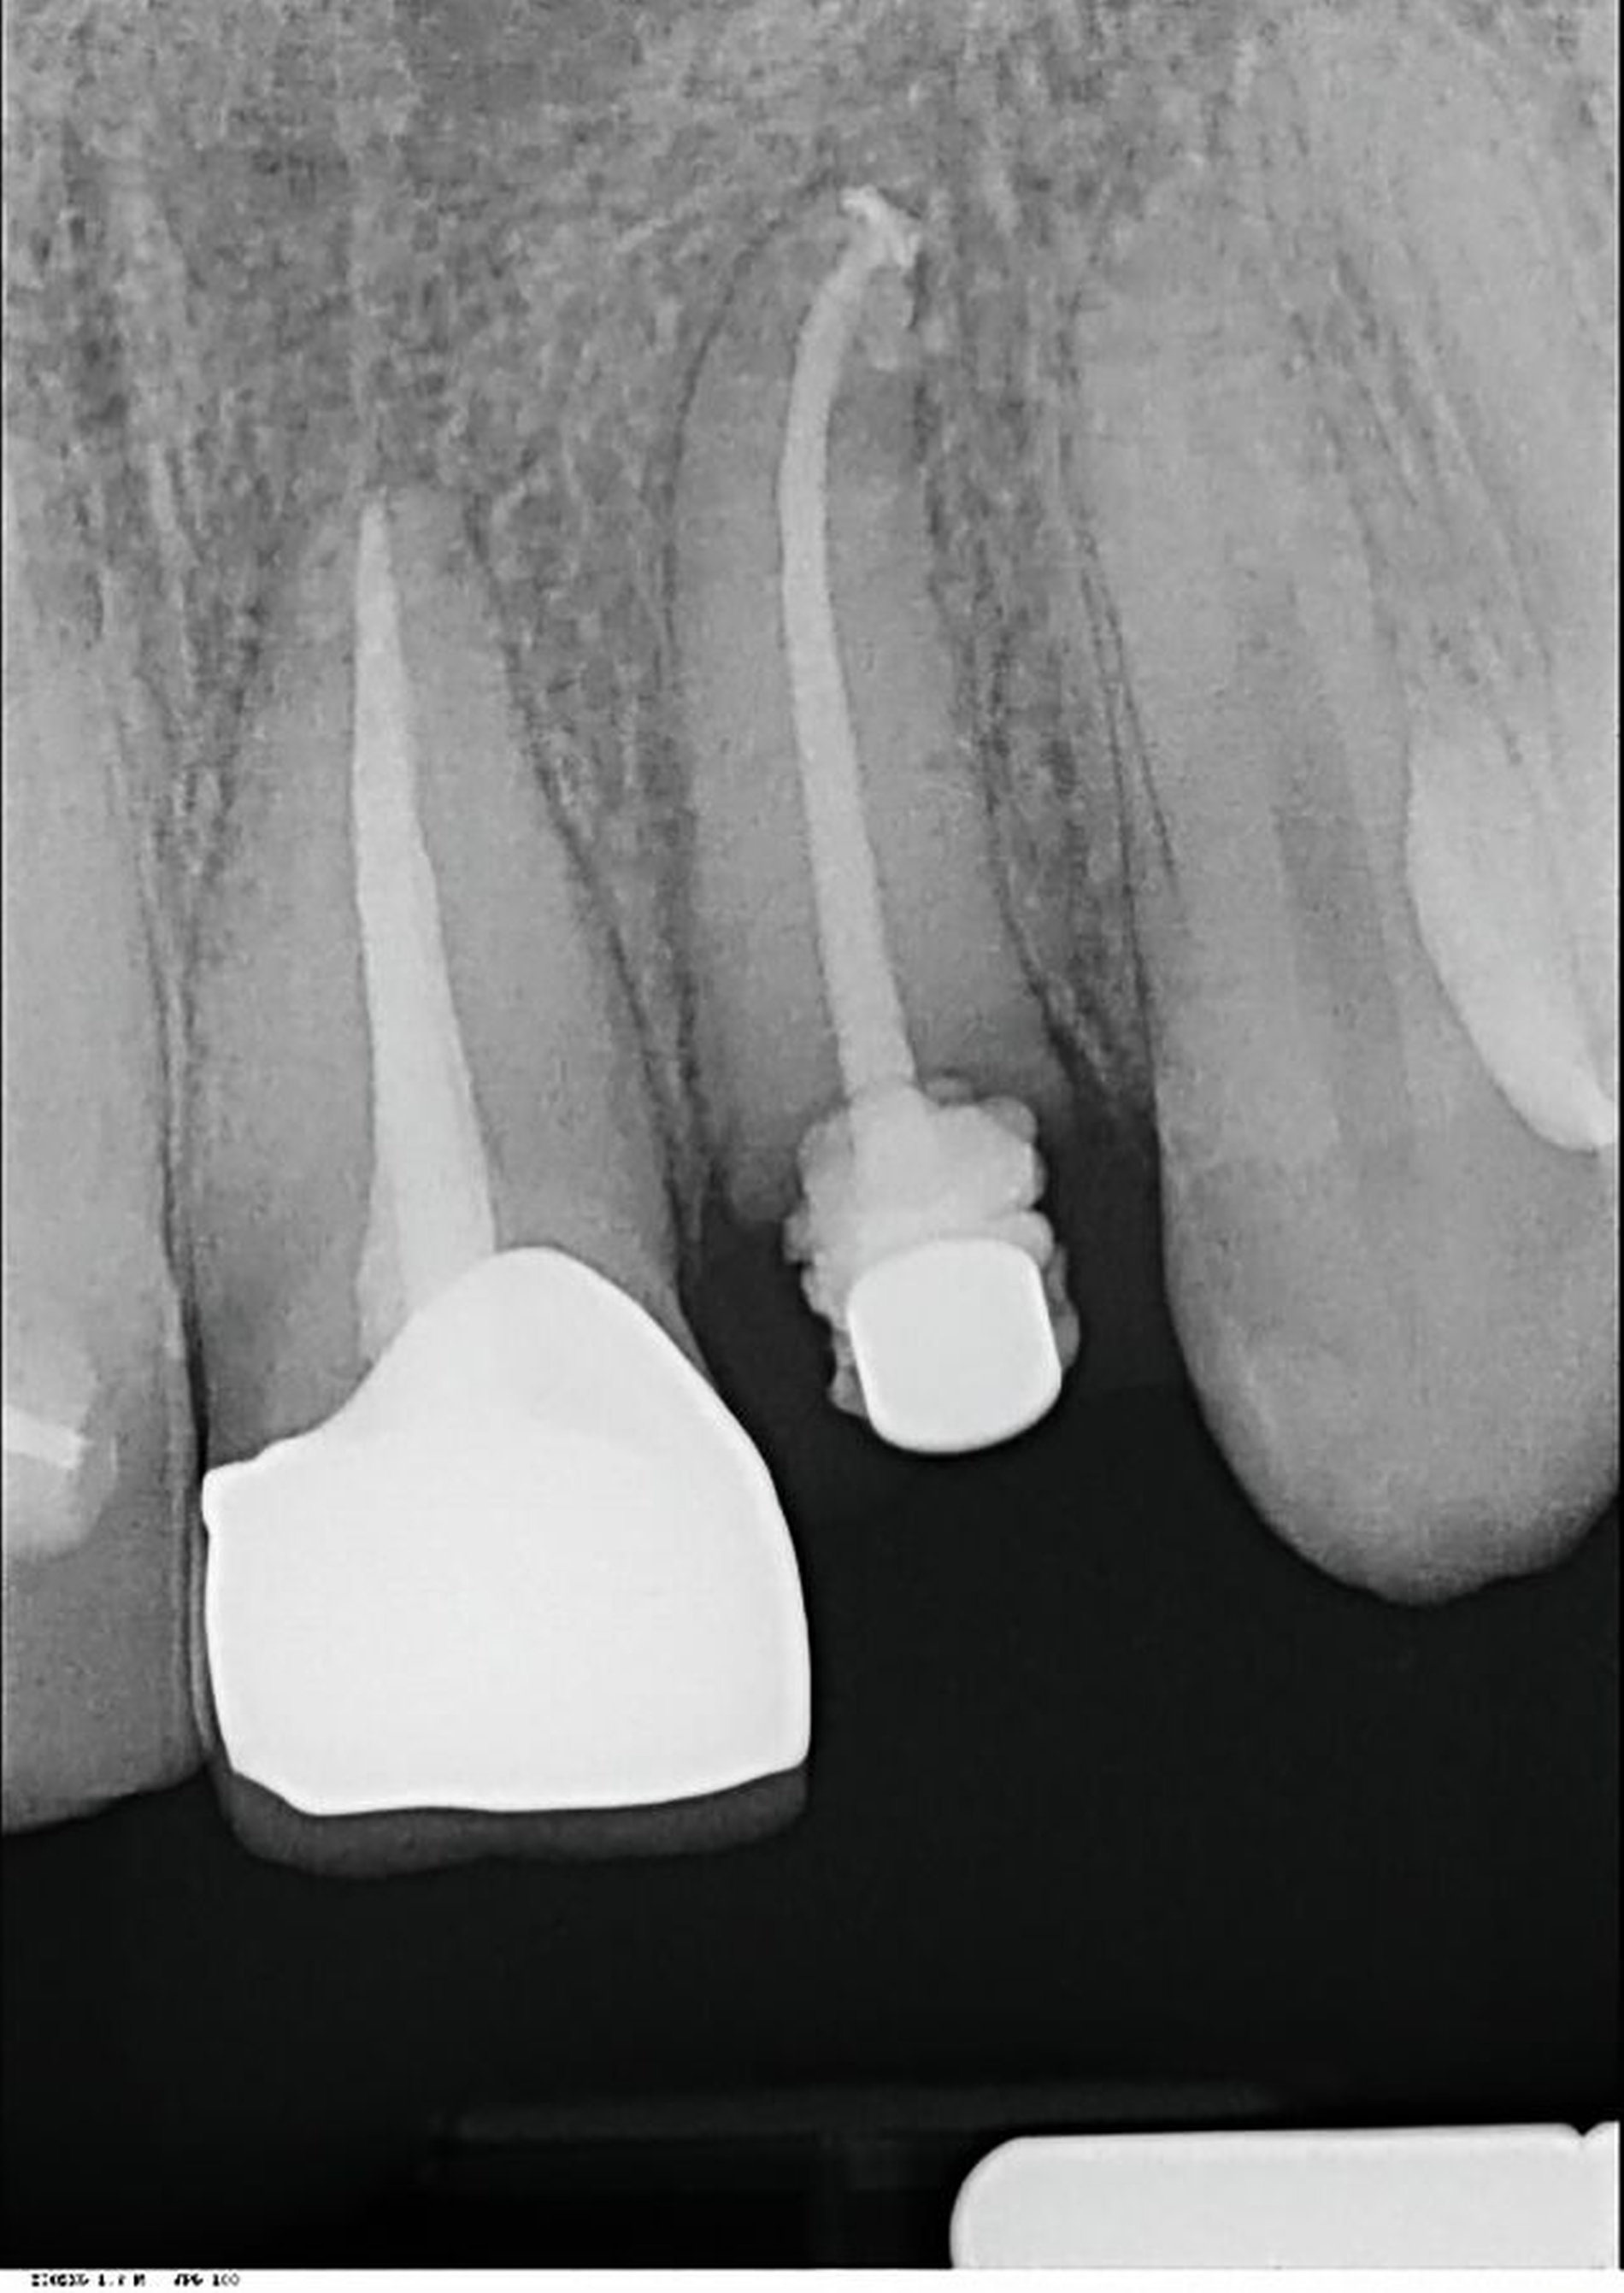

Anhand der von uns durchgeführten Einzelzahnaufnahme konnte die alio loco gestellte Erstdiagnose korrigiert werden: Wurzelfraktur des Zahnes 22 mit Kommunikation zur Mundhöhle (Abbildung 19). Der Patient favorisierte nach Diagnosesicherung zunächst Zahnersatz an 22 durch ein Sofortimplantat, weshalb eine DVT-Aufnahme zur weiteren Planung angefertigt wurde (Abbildung 20). In der Aufnahme zeigte sich jedoch, dass keine suffiziente vestibuläre Knochenlamelle vorhanden und somit der Erfolg eines Sofortimplantats nicht sicher vorhersagbar war. Nach umfassender Aufklärung entschied sich der Patient für den Zahnerhalt und eine Extrusion mit Magneten (Abbildungen 21 bis 24).

Nachdem eine Wurzelkanalbehandlung durchgeführt worden war, wurde der Magnet adhäsiv befestigt und die Zahnwurzel bis circa 4 mm über das Knochenniveau bewegt. Hierfür waren wochenweise Recalltermine notwendig, um den Magneten in der Schiene umzupositionieren und durch suprakrestale Fibrotomie die parodontalen Fasern zu lösen (Abbildung 22 und 23).

Als die Wurzel des Zahnes 22 ausreichend extrudiert war, wurde ein adhäsiver Stift-Stumpf-Aufbau inseriert (Abbildungen 24 und 25). Die Krone an Zahn 21 wurde entfernt, da diese durch das Trauma inzisal beschädigt worden war und der Patient eine Neuanfertigung wünschte.

In Fall 2 wurde die Extrusion mit einem Magneten durchgeführt. Hier wird mittels Säure-Ätz-Technik ein Magnet mit 3 mm Durchmesser auf den verbliebenen Wurzelrest geklebt. Der Gegenmagnet wurde im Abstand von circa 2 mm in eine Tiefziehschiene einpolymerisiert. Dadurch war der Patient gleichzeitig für die Extrusionszeit provisorisch versorgt. Hilfreich ist hier ein im Vorfeld angefertigter, wenig resilienter Platzhalter. Des Weiteren hat dieses Vorgehen den Vorteil, dass die axiale Ausrichtung bereits optimal angepasst werden kann. Nach Bedarf sollten der Magnet weiter nach inzisal versetzt und eine Fibrotomie durchgeführt werden, bis der Wurzelrest ausreichend extrudiert ist.